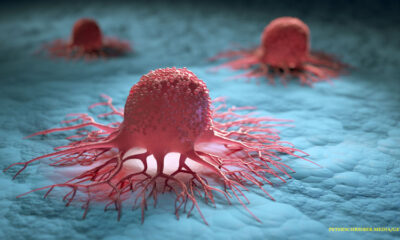

Cancer vaccinations already exist, but your doctor may not tell you about them until you ask

Cancer vaccines are a concept that appears to have been torn from the plot of a...

A cancer-killing virus was injected into humans for the first time to improve outcomes for patients in their battle with cancer

City of Hope and Imugene Limited, a clinical-stage immuno-oncology company, reported today that the first patient...